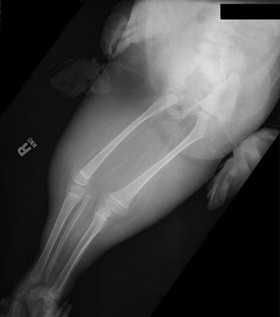

Hình ảnh chụp X quang cho thấy chân của Shiloh bị dính vào nhau. Ảnh chụp năm cô bé 4 tuổi. |